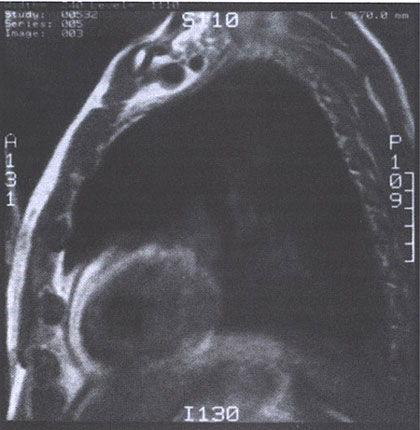

Figure 38 j MRI scan (spin-echo image) from a patient

with constrictive pericarditis. The pericardium is viewed as a Line of

low signal intensity (black) sandwiched between higher-intensity epicardial

and pericardial fat (white). Note the regional variation of pericardial

thickness, which is normally 1 to 2 mm. (From Hoit BD. Pericardial disease and pericardial heart disease. In: ORourke RA ed. Stein's Internal Medicine, 5th ed. St. Louis, Missouri: MosbyYear Book;1998:273. |